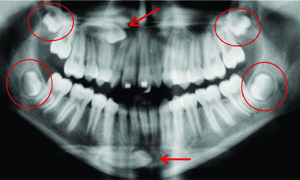

Ortodontia e Ortopedia